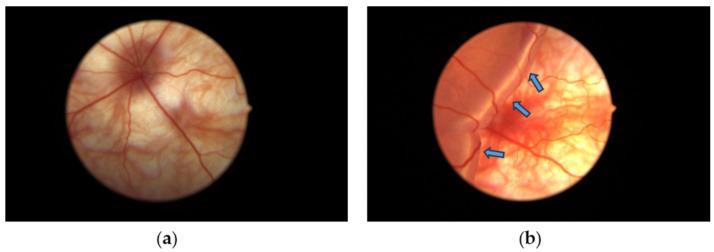

Retinal detachment (RD) can result in the loss of photoreceptors that cause vision impairment and potential blindness. This study explores the protective effects of the oral administration of green tea extract (GTE) in a rat model of RD. Various doses of GTE or epigallocatechin gallate (EGCG), the most active ingredient in green tea catechins, were administered to Sprague Dawley (SD) rats with experimentally induced retinal detachment. The rats received sub-retinal injections of hyaluronic acid (0.1%) to induce RD and were given different doses of GTE and EGCG twice daily for three days. Notably, a low dose of GTE (142.9 mg/kg) caused significantly higher signal amplitudes in electroretinograms (ERGs) compared to higher GTE doses and any doses of EGCG. After administration of a low dose of GTE, the outer nuclear layer thickness, following normalization, of the detached retina reduced to 82.4 ± 8.2% (Mean ± SEM, < 0.05) of the thickness by RD treatment. This thickness was similar to non-RD conditions, at 83.5 ± 4.7% (Mean ± SEM) of the thickness following RD treatment. In addition, the number of TUNEL-positive cells decreased from 76.7 ± 7.4 to 4.7 ± 1.02 (Mean ± SEM, < 0.0001). This reduction was associated with the inhibition of apoptosis through decreased sphingomyelin levels and mitigation of oxidative stress shown by a lowered protein carbonyl level, which may involve suppression of HIF-1α pathways. Furthermore, GTE showed anti-inflammatory effects by reducing inflammatory cytokines and increasing resolving cytokines. In conclusion, low-dose GTE, but not EGCG, significantly alleviated RD-induced apoptosis, oxidative stress, inflammation, and energy insufficiency within a short period and without affecting energy metabolism. These findings suggest the potential of low-dose GTE as a protective agent for the retina in RD.

视网膜脱离(RD)可导致光感受器丧失,进而引起视力损害甚至失明。本研究探讨口服绿茶提取物(GTE)对RD大鼠模型的保护作用。将不同剂量的GTE或表没食子儿茶素没食子酸酯(EGCG,绿茶儿茶素中最具活性的成分)给予实验性诱导视网膜脱离的Sprague Dawley(SD)大鼠。大鼠接受玻璃体内注射透明质酸(0.1%)以诱导RD,并连续三天每天两次给予不同剂量的GTE和EGCG。值得注意的是,与较高剂量的GTE和任何剂量的EGCG相比,低剂量的GTE(142.9 mg/kg)在视网膜电图(ERG)中引起显著更高的信号幅度。给予低剂量的GTE后,脱离视网膜经标准化后的外核层厚度降至RD治疗后厚度的82.4±8.2%(平均值±标准误,P<0.05)。该厚度与非RD条件相似,为RD治疗后厚度的83.5±4.7%(平均值±标准误)。此外,TUNEL阳性细胞数量从76.7±7.4降至4.7±1.02(平均值±标准误,P<0.0001)。这种减少与通过降低鞘磷脂水平抑制细胞凋亡以及通过降低蛋白质羰基水平减轻氧化应激有关,这可能涉及抑制HIF-1α通路。此外,GTE通过减少炎性细胞因子和增加消退性细胞因子表现出抗炎作用。总之,低剂量的GTE而非EGCG在短时间内显著减轻了RD诱导的细胞凋亡、氧化应激、炎症和能量不足,且不影响能量代谢。这些发现表明低剂量GTE作为RD中视网膜保护剂的潜力。